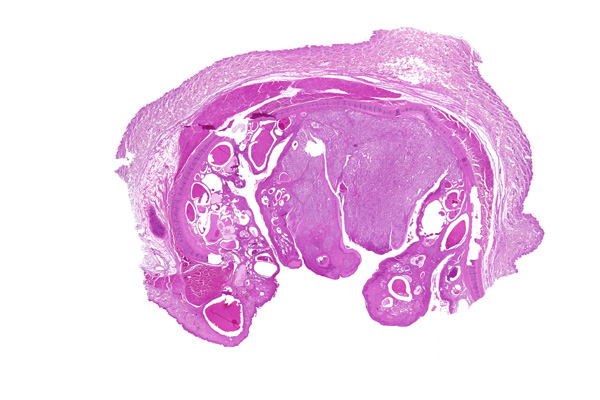

These glands are capable of developing both benign and malignant tumors. The benign tumors include ceruminous adenoma, ceruminous pleomorphic adenoma, and ceruminous syringocystadenoma papilliferum. The malignant tumors include ceruminous adenocarcinoma, adenoid cystic carcinoma, and mucoepidermoid carcinoma.